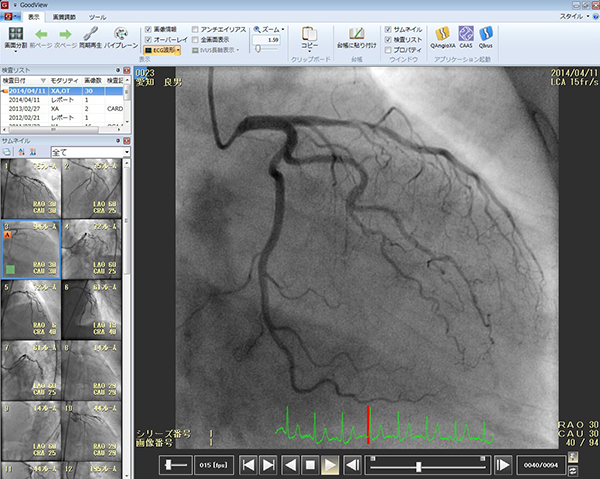

<DICOM動画像ビューワ「GoodView」>

GOODNET専用ビューワとWebビューワとも操作性を統一し,Bi-Plane画像を自動判断して2画面表示するBi-Planeモードや,IVUS長軸構築,DICOM CDビューワなど,さらに機能を充実させました。また画像処理やアノテーション表示,さらにフレーム単位の編集処理を施した後,静止画や動画の各種ファイルフォーマットへ変換する機能も統合しており,スタンドアロンのビューワとしてもお使いいただけます。

GoodView:動画像ビューワ